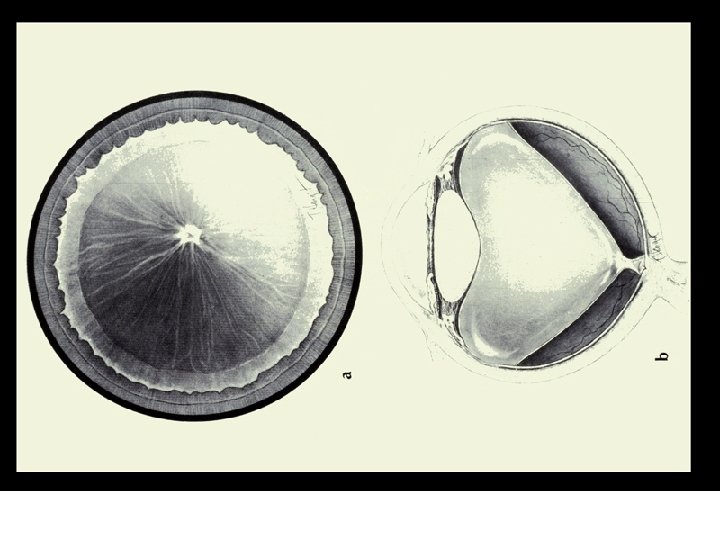

VII. PATHOLOGY AND AGE RELATED CHANGES z. A. Aging Changes y 1. Syneresis xa. a breakdown of the vitreous gel xb. fluid filled cavities form xc. 65 % of those over the age of 60 have syneresis xd. higher incidence in myopes

VII. PATHOLOGY AND AGE RELATED CHANGES xe. results in the fluid filled cavities enlarging and a possibility of the vitreous detaching from the retina xf. with detachment the patient reports "flashing lights" and "floaters" xg. more prone to retinal detachment